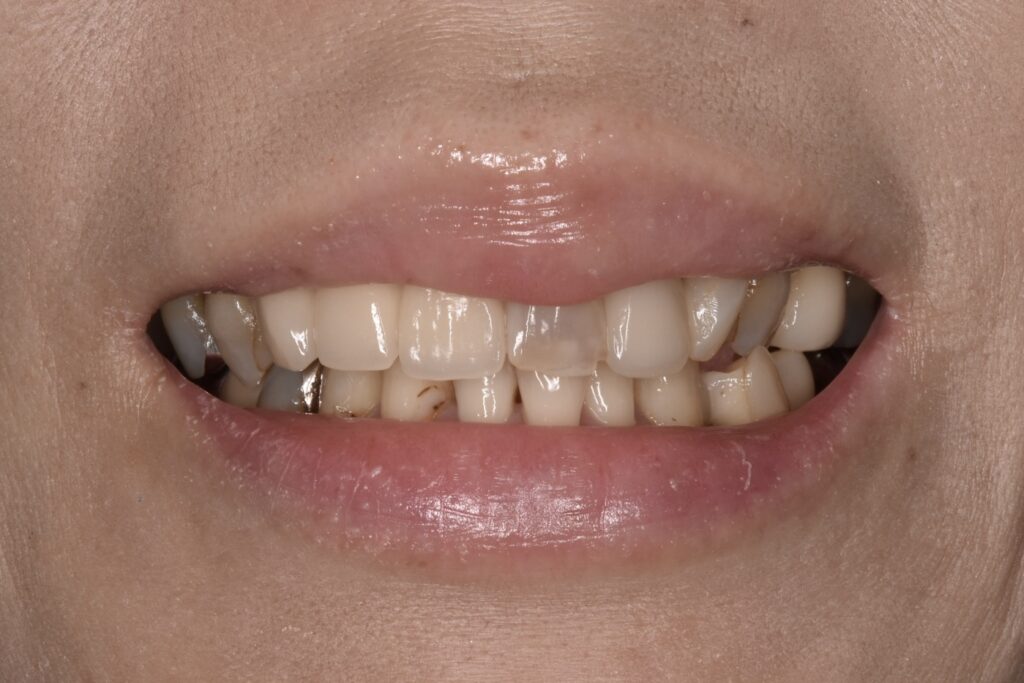

初診時の状態

各歯が自費の被せ物や保険の治療痕など歯ごとにバラバラな状態で、どれも状態が良いとは言えないものばかりでした。見た目の回復も必要ですがそれ以前に再神経処置・虫歯再治療・抜歯、噛み合わせの回復など多岐にわたる治療が必要な状態でした。

今回は上をメインに治療し下の歯は順次治療していきます。(そのようにご希望です)